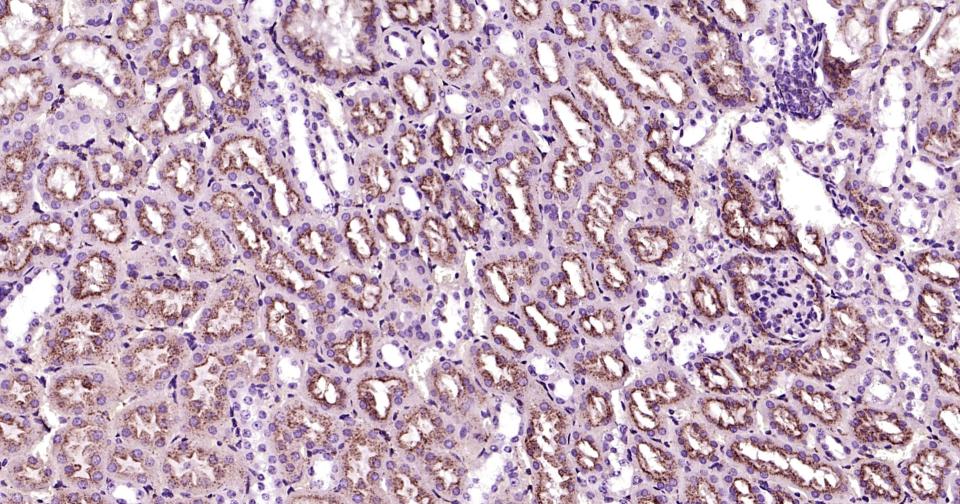

Paraformaldehyde-fixed, paraffin embedded Human liver;Antigen retrieval by boiling in sodium citrate buffer (pH6.0) for 15 min; Antibody incubation with LAMP2 Monoclonal Antibody, Unconjugated (bsm-61207R) at 1:200 overnight at 4°C, followed by conjugation to the bs-0295G-HRP and DAB (C-0010) staining.